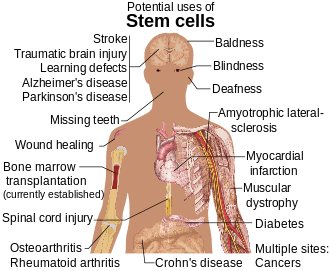

Treatment

Diseases and conditions where stem cell treatment is being investigated include:

- Diabetes[66]

- Rheumatoid arthritis[66]

- Parkinson's disease[66]

- Alzheimer's disease[66]

- Osteoarthritis[66]

- Stroke and traumatic brain injury repair[67]

- Learning disability due to congenital disorder [68]

- Spinal cord injury repair [69]

- Heart infarction [70]

- Anti-cancer treatments [71]

- Baldness reversal[72]

- Replace missing teeth [73]

- Repair hearing [74]

- Restore vision [75] and repair damage to the cornea[76]

- Amyotrophic lateral sclerosis [77]

- Crohn's disease [78]

- Wound healing [79]

- Male infertility due to absence of spermatogonial stem cells [80]

Research is underway to develop various sources for stem cells, and to apply stem cell treatments for neurodegenerative diseases and conditions, diabetes, heart disease, and other conditions.[81]